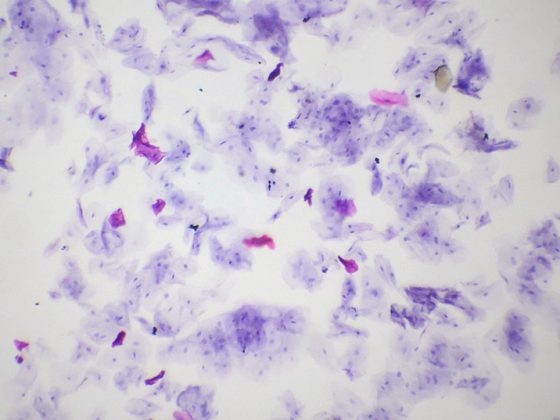

Der tenosynoviale Riesenzelltumor ist eine seltene gutartige Erkrankung der Gelenkinnenhaut, bei der es zu einer ausgeprägten Gewebevermehrung kommt. Eine diffuse Gelenkzerstörung mit nachfolgender Invalidität kann die Folge sein. Die Zukunft könnte der Therapie mit Tyrosinkinase-Inhibitoren gehören.